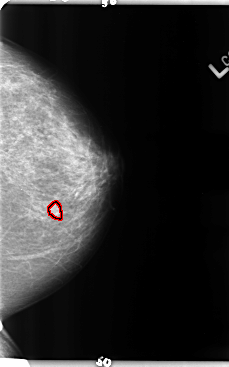

FILE: B_3158_1.LEFT_MLO.OVERLAY

TOTAL_ABNORMALITIES 1

ABNORMALITY 1

LESION_TYPE MASS SHAPE LOBULATED MARGINS CIRCUMSCRIBED-OBSCURED

ASSESSMENT 3

SUBTLETY 2

PATHOLOGY BENIGN

TOTAL_OUTLINES 1

BOUNDARY